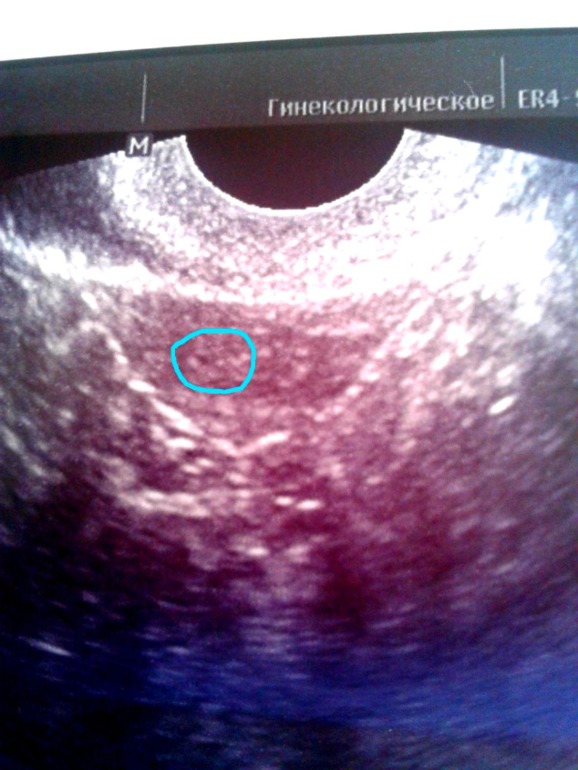

Повторите узи через неделю. У меня так тоже когда-то было. Задержка пипец какая, тесты полосатые, хгч- 7-8 недель, а в матке и трубах пусто. Главное не отчаиваться и работать над процессом.

У меня только один вопрос. - как??? Может была Б просто не удержалась? Иначе с чего бы?

Для меня это тоже до сих пор загадка. Врачи предполагают разное: ЗБ, гормональный сбой, и все разводят руками. Может такая узистка была "замечательная". Не знаю. Было и прошло.